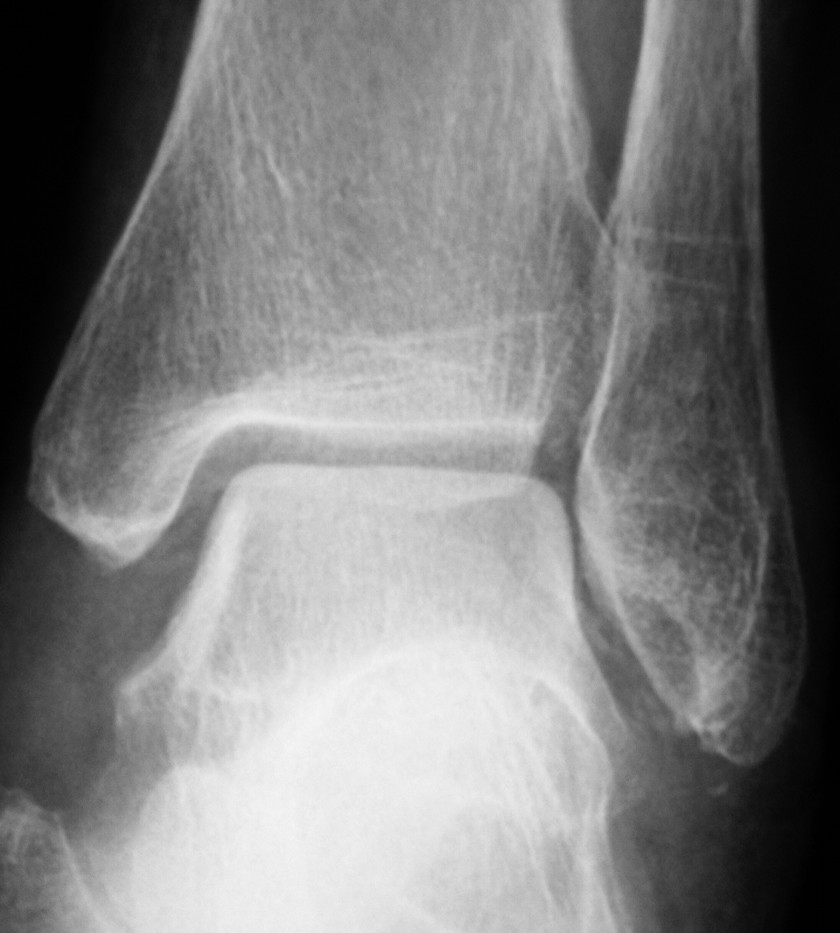

80代の症例。7月末に「坐骨神経痛」と整骨院で診断されて足くびをマッサージをされたとか。

それ以降、左側優位の足関節腫脹出現。近所の整形外科を受診。特に足関節に言及ナシだったとか。

薬剤を処方されるも、腫脹回復せず、友人からの紹介で当院受診。Xp上、異常確認。

投薬開始。

80代の症例。7月末に「坐骨神経痛」と整骨院で診断されて足くびをマッサージをされたとか。それ以降、左側優位の足関節腫脹出現。近所の整形外科を受診。特に足関節に言及ナシだったとか。